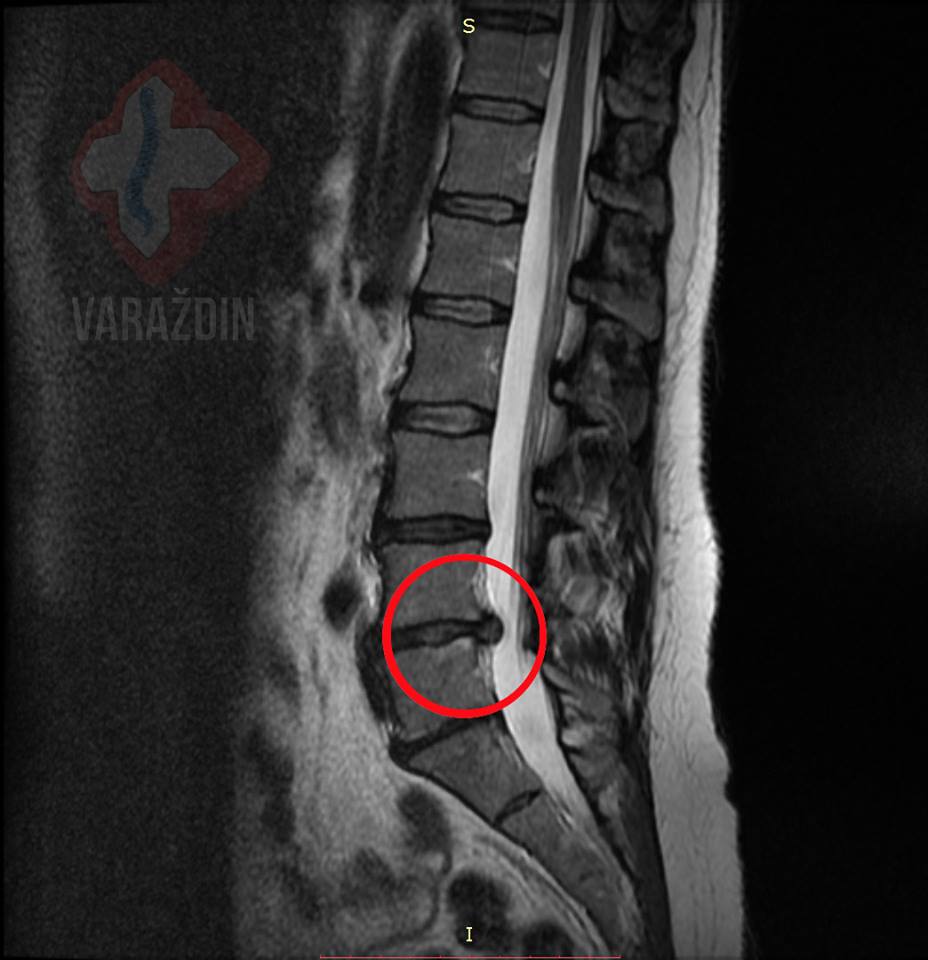

Gospođa Višnja Božić javila nam se zbog izuzetno

jakih bolova koji su sezali iz lumbalnog područja kralježnice duž

desne noge, uz također u nozi prisutne trnce.

Zajedničkom odlukom krenuli smo na tretiranje lumbalne

kralježnice putem dekompresijskih tretmana. U nadi smanjenja

simptoma odluka je pala na 15-tak tretmana zbog izrazitog

ispupčenja diska na desnu stranu.

Strpljenje gospođe Božić urodilo je plodom: maksimalnom sanacijom

njenog problema. Bol i trnci u desnoj nozi potpuno su nestali.

Zahvaljujemo se na ukazanom povjerenju gospođi Višnji, a

rezultate i efekt tretmana vidjeti možete na slikama MR uz

objavu.